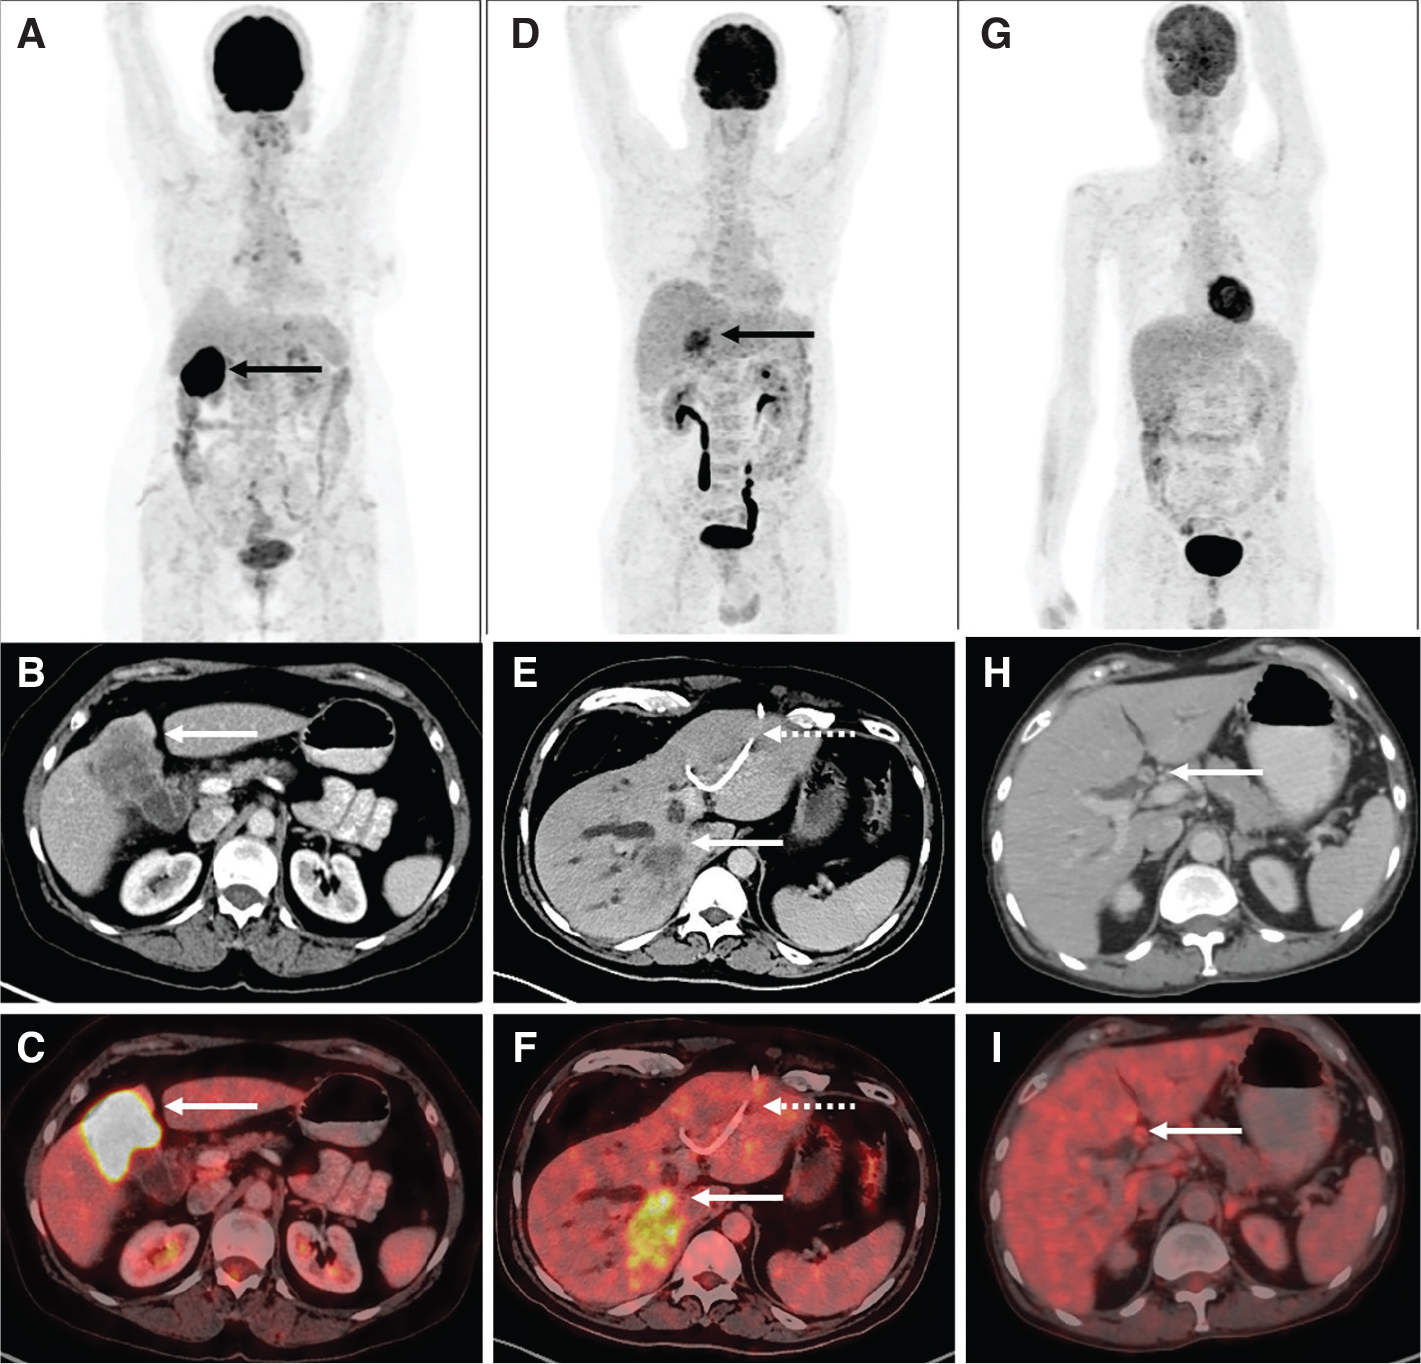

Various PET quantitative parameters such as SUV, metabolic tumor volume (MTV) and tumor lesion glycolysis (TLG) accurately detect the baseline tumor bulk and total body disease burden and have a significant role in disease prognosis and management (48). The primary tumor SUVmax is an independent prognostic factor for survival outcomes in CCA and for predicting metastases on follow-up (48). Calculating volumetric parameters is tedious and time consuming, however technological advances in the form of automated volumetric analysis and threshold-based segmentation have made it more convenient. Newer acquisition techniques like dynamic 18F-FDG PET imaging have shown to be superior to conventional imaging in detecting and excluding CCA in advanced PSC with lesion/liver ratio being significantly higher in parametric images than static PET images (49). Not only can it help to differentiate normal from malignant tissue, kinetic modeling and analysis also helps to differentiate hepatocellular cancer from CCA (50). Figure 3 shows 18F-FDG PET-CT findings in common BTCs.

Fig 1

Figure 3. 18F-FDG PET/CT in biliary tract cancers: A) Maximum Intensity Projection (MIP) image showing focal intense tracer uptake in the region of the gallbladder fossa (black arrow). Corresponding CT (B) and fused PET/CT (C) images show intensely tracer avid (SUVmax 28.7) heterogeneously enhancing mass lesion arising from the fundus and body of the gallbladder with local invasion (Gallbladder carcinoma) (white arrows). D) MIP image showing tracer uptake in the region of the liver (black arrow) with corresponding CT (E) and fused PET/CT (F) images showing 18F-FDG avid (SUVmax 11.2) hypodense lesion in the right lobe of liver (white arrows) causing intrahepatic biliary radical dilatation suggestive of intrahepatic cholangiocarcinoma along with percutaneous transhepatic biliary duct stent in situ in the left ductal system (dotted arrows). G) MIP image with no abnormal focus of uptake seen anywhere in the region of the liver. Corresponding CT (H) and fused PET/CT (I) images show faintly tracer avid biliary ductal thickening (SUVmax 5.1) in the hilar region with tracer uptake similar to background liver uptake suggestive of hilar cholangiocarcinoma.